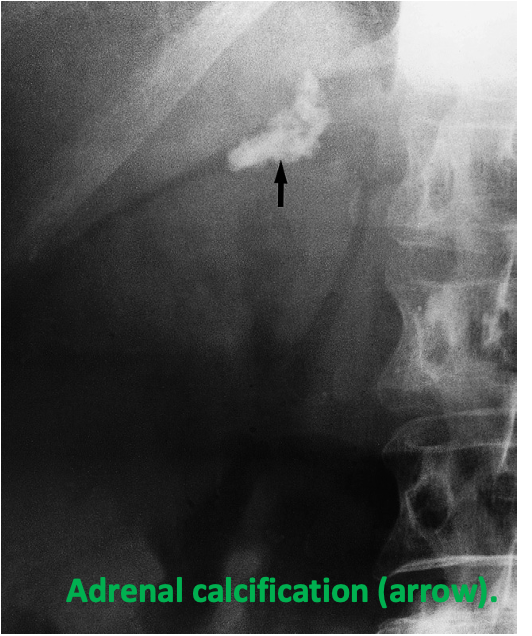

Occurs after adrenal haemorrhage, after tuberculosis and occasionally in adrenal tumours